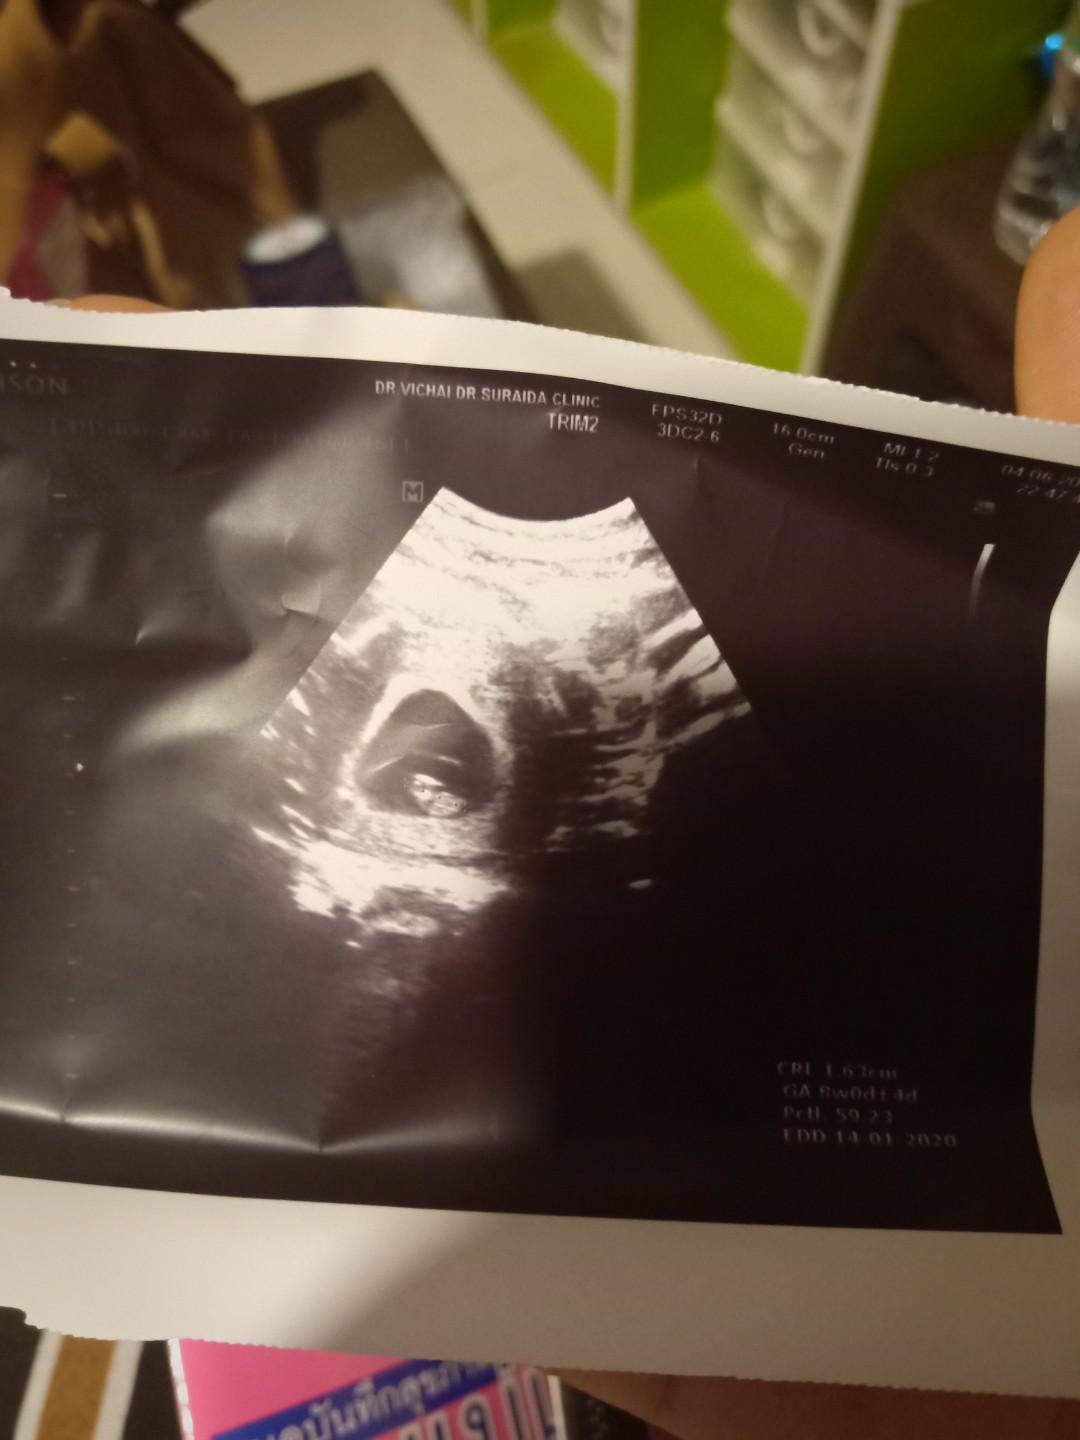

8w พอดีค่ะภาพแรก ตอนนี้ 10wค่ะ

ตอน 8 วีคค่ะ ตอนนี้ 33 วีค 5 วันค่ะ

ท้องแรก ตอนนี้14วีคแล้วค่ะ 💜

4ปีที่รอคอยค่ะ รู้ตัวก็10wแล้ว

ภาพแรกของหนู ตอนอายุครรภ์ 7W6D

ซาวตอน8weekตอนนี้36weekแล้วจ้า

ภาพแรกตอน 10 week จ้า ตอนนี้ 25 week

ตอน5วีค คะ ตอนนี้ 17+3เเล้วคะ

ตอน12วีคคะ ตอนนี้20วีคแล้ว

ภาพแรกตอน 3 เดือนค่ะ